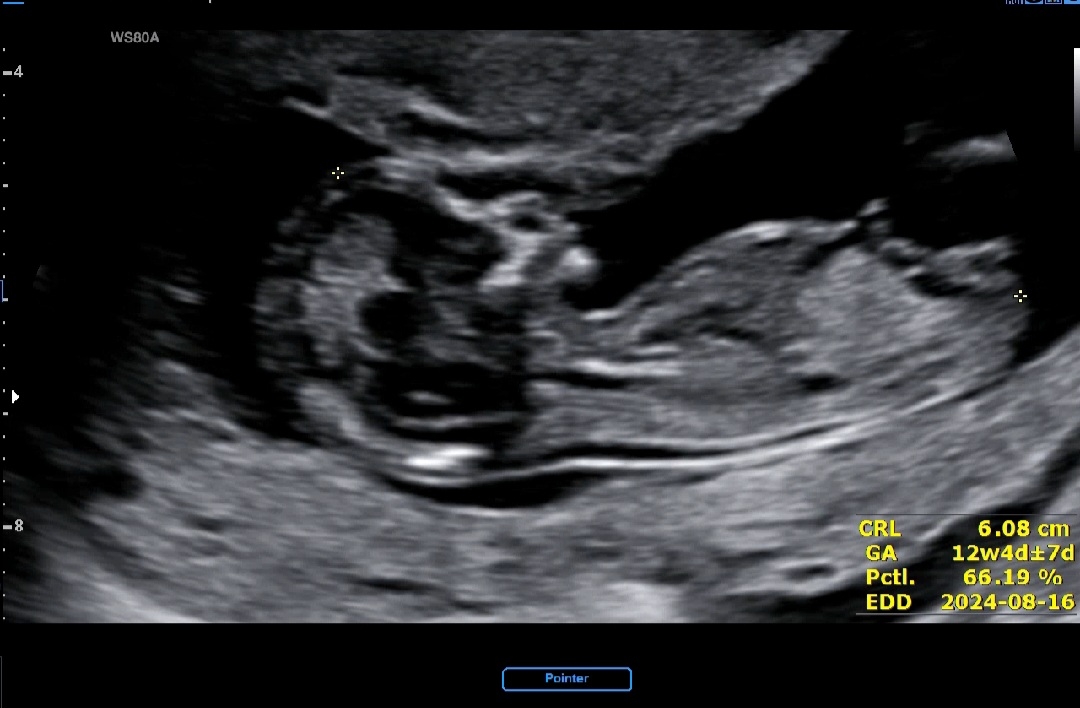

12주4일차 각도법 봐주세요!

12주4일차 각도법 마구마구 봐주세요오!!! 😃